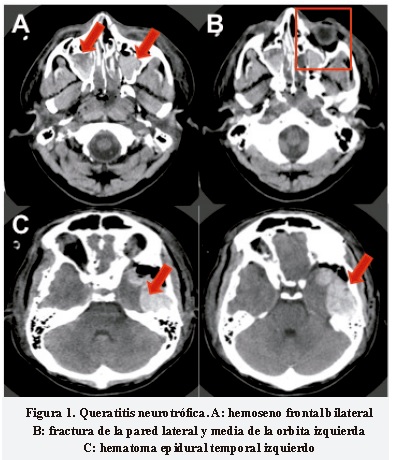

Paciente masculino de 30 años, que en abril de 2011 sufrió accidente de tránsito en calidad de conductor de motocicleta, con golpe contuso en el rostro. Ingresó al servicio de urgencias con Glasgow inicial 11/15 por traumatismo encefalocraneano (TEC) severo. Se realizó tomografía axial computada (TAC) de cráneo y rostro en la cual se evidenció: hematoma epidural temporal izquierdo con efecto de masa y edema cerebral generalizado. Además, múltiples fracturas de huesos craneales (temporo-parietal bilateral y fractura transversa de mastoides bilaterales, fractura de piso de órbita, pared lateral y media) (Figura 1), hemoseno frontal, esfenoidal y maxilar bilateral. Por los hallazgos anteriores y deterioro de su estado neurológico con disminución del Glasgow a 7/15, se llevó a cirugía para drenaje quirúrgico del hematoma epidural y mastoidectomía más liberación de VII par izquierdo. Permaneció en unidad de cuidado intensivo durante 11 días con soporte ventilatorio y sedación. Sale de alta luego de 14 días con amnesia de 1 semana periepisodio, no percepción de la luz (NPL) en ojo izquierdo (OI) por neuropatía óptica traumática, úlcera corneal en ojo derecho (OD) por alteración sensitiva córneo-conjuntival del V1, úlcera corneal por exposición en OI y parálisis facial ipsilateral secundaria a lesión de VII par izquierdo, tinitus bilateral y pérdida de audición en oído derecho.